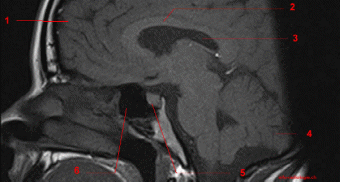

Магнитно-резонансная томография. Наиболее информативный метод исследования гипофиза. При магнитно-резонансной томографии визуализируются передняя и задняя доли, воронка гипофиза, возможно оценить симметричность гипофиза, положение воронки, состояние спинки турецкого седла. На МР-сканах структура аденогипофиза гомогенная, изоинтенсивна с белым веществом мозга.

Аденомы гипофиза на Т1 ВИ – визуализируются как зоны со сниженным по сравнению с остальной тканью аденогипофиза сигналом, на Т2ВИ – как зоны с повышенным сигналом. При внутривенном контрастировании аденомы накапливают контрастное вещество и можно более детально оценить структуру опухоли.

Рисунок Магнитно-резонансная томограмма гипофиза и области турецкого седла: 1 – лобная доля; 2 – мозолистое тело; 3 – боковой желудочек; 4 – мозжечок; 5 – гипофиз; 6 – клиновидная пазуха.

Рисунок Магнитно-резонансные томограммы головного мозга

Рисунок Магнитно-резонансная томограмма головного мозга в коронарной плоскости: аденома гипофиза

Рисунок Магнитно-резонансная томограмма головного мозга в сагиттальной плоскости. Микроаденома.

Рисунок Магнитно-резонансная томограмма головного мозга в сагиттальной плоскости. Макроаденома.